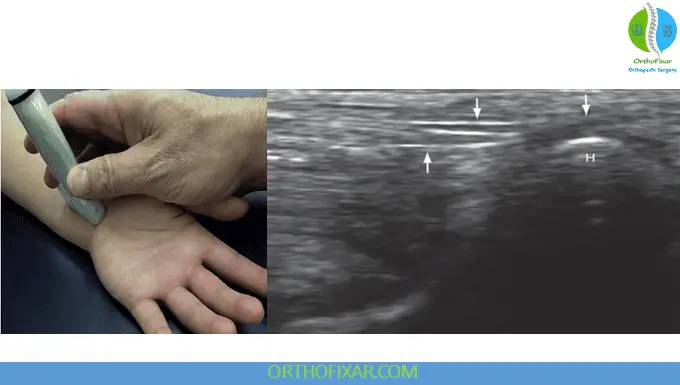

The ulnar side of the anterior wrist houses the ulnar nerve, artery, and vein. The pisiform bone serves as a crucial landmark for locating these structures. The ulnar nerve appears between the pisiform and ulnar artery, displaying the same honeycomb pattern of hypoechoic fascicles surrounded by hyperechoic connective tissue seen in the median nerve.

Clinical Significance of the Hook of Hamate: Moving distally, the hook of the hamate becomes visible and represents a critical anatomical region. Hamate fractures commonly occur during:

These injuries can cause compression of surrounding nerves and arteries, making ultrasound assessment valuable for both diagnosis and monitoring.

Ulnar Nerve Branches: In short axis, the ulnar nerve branches can be observed coursing around the hamate, with the deep motor branch on the ulnar side and the sensory branch superficial to the hamate.